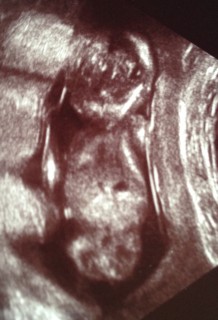

体外受精33回目にしての今のところ順調な妊娠生活。今日は、背骨の一本一本、肋骨も見えました!人間の生命力はすごいです!BPD24ミリです。